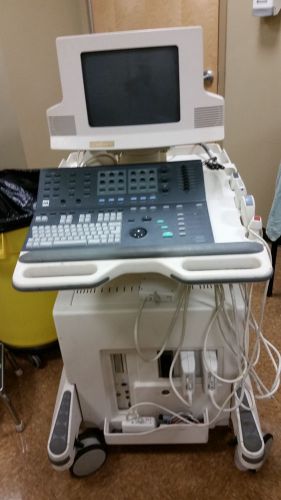

ATL HDI 5000 Diagnostic Centrifuge